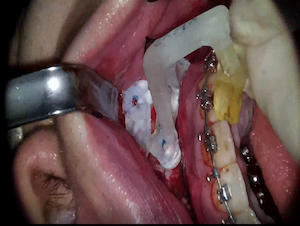

Ten implants placement with predictable computer guided surgery

Dr. NATALIA KOSIUK,Edentulous,Aesthetic zone,Digital Guided Surgery,Immediate loading,Maxillary Anteiror,Maxillary Posterior,#12,#13,#15,#22,#23,#25,#34,#34,#44,#46,Immediate Placement,Flapless,Guided surgery,R2GATE Guide,MEGA ISQ,Poster